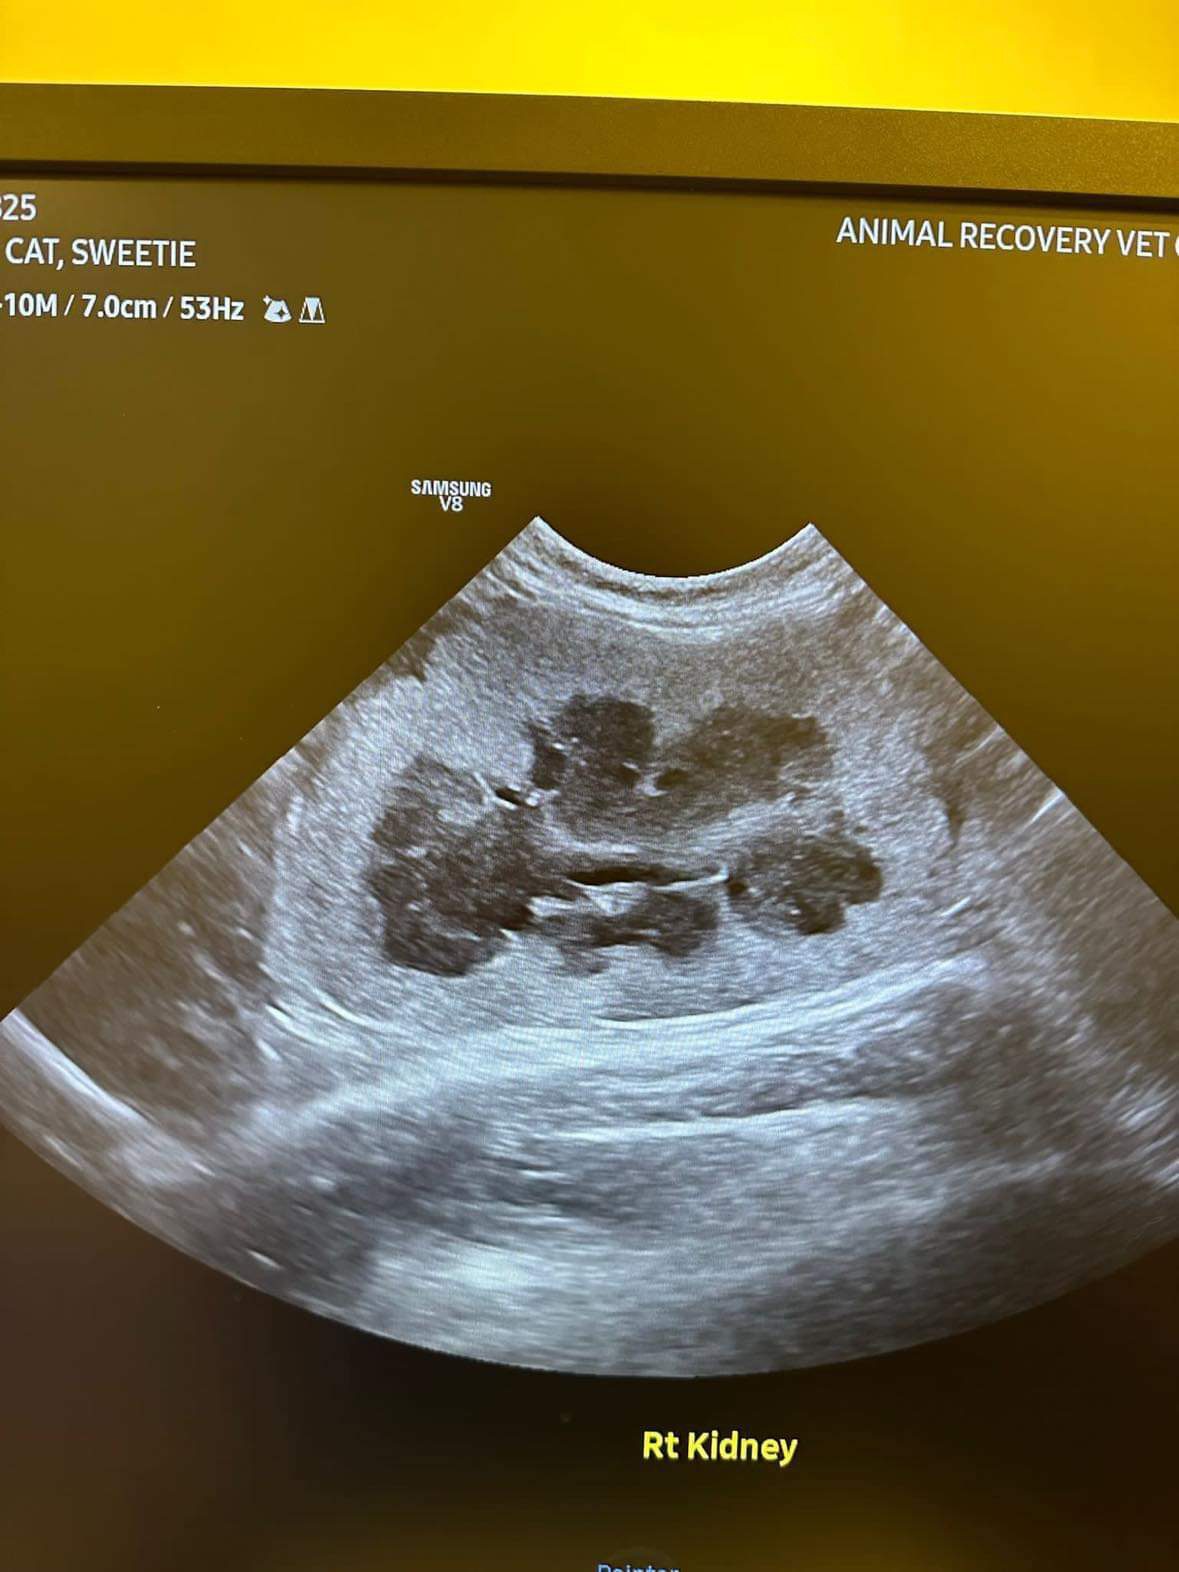

U/s done and basically not much use to me, liver got issue, kidneys got some fatty deposits which is diabetic, so insulin correct. Gall bladder got some obstruction so just start urofalk. All in must put o tube. Dr Daniel do it.

her left kidney 8.0cm, right 7.0cm also double the normal size

Dr ym scan sweeties, dr flo not involve, both got free fluid ard the kidneys, left kidney is extremely abnormal, right kidney abnormal.